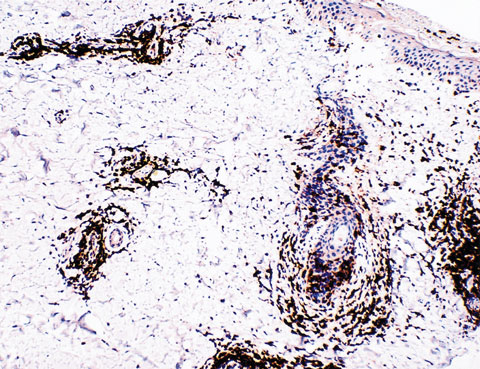

Skinprick, intradermal and subcutaneous testing with normal saline, the amide anaesthetics lignocaine and citanest, and the ester anaesthetic procaine showed no evidence of an immediate type 1 allergic reaction. However, two days later the patient reported that a raised area of skin had appeared. Subcutaneous injection with lignocaine resulted in a localised raised erythematous rash 48 hours after injection. A less intense reaction occurred with citanest, and no reaction was detected with procaine or normal saline alone. Histopathology of the skin biopsy from the lignocaine challenge site is shown in Boxes 1 and 2.

This patient demonstrated a DTH reaction to two agents from the amide class of anaesthetics. Presumably, sensitisation to lignocaine had occurred at the time of previous procedures using the agent. Cross-reactivity with another amide-type local anaesthetic is the most likely explanation for the less intense reaction seen with citanest. Although DTH reactions to local anaesthetics are rare, this case highlights the fact that DTH reactions should be considered in the differential diagnosis of local reactions after procedures using local anaesthesia. This may avoid unnecessary investigations, misdiagnoses and inappropriate treatment.